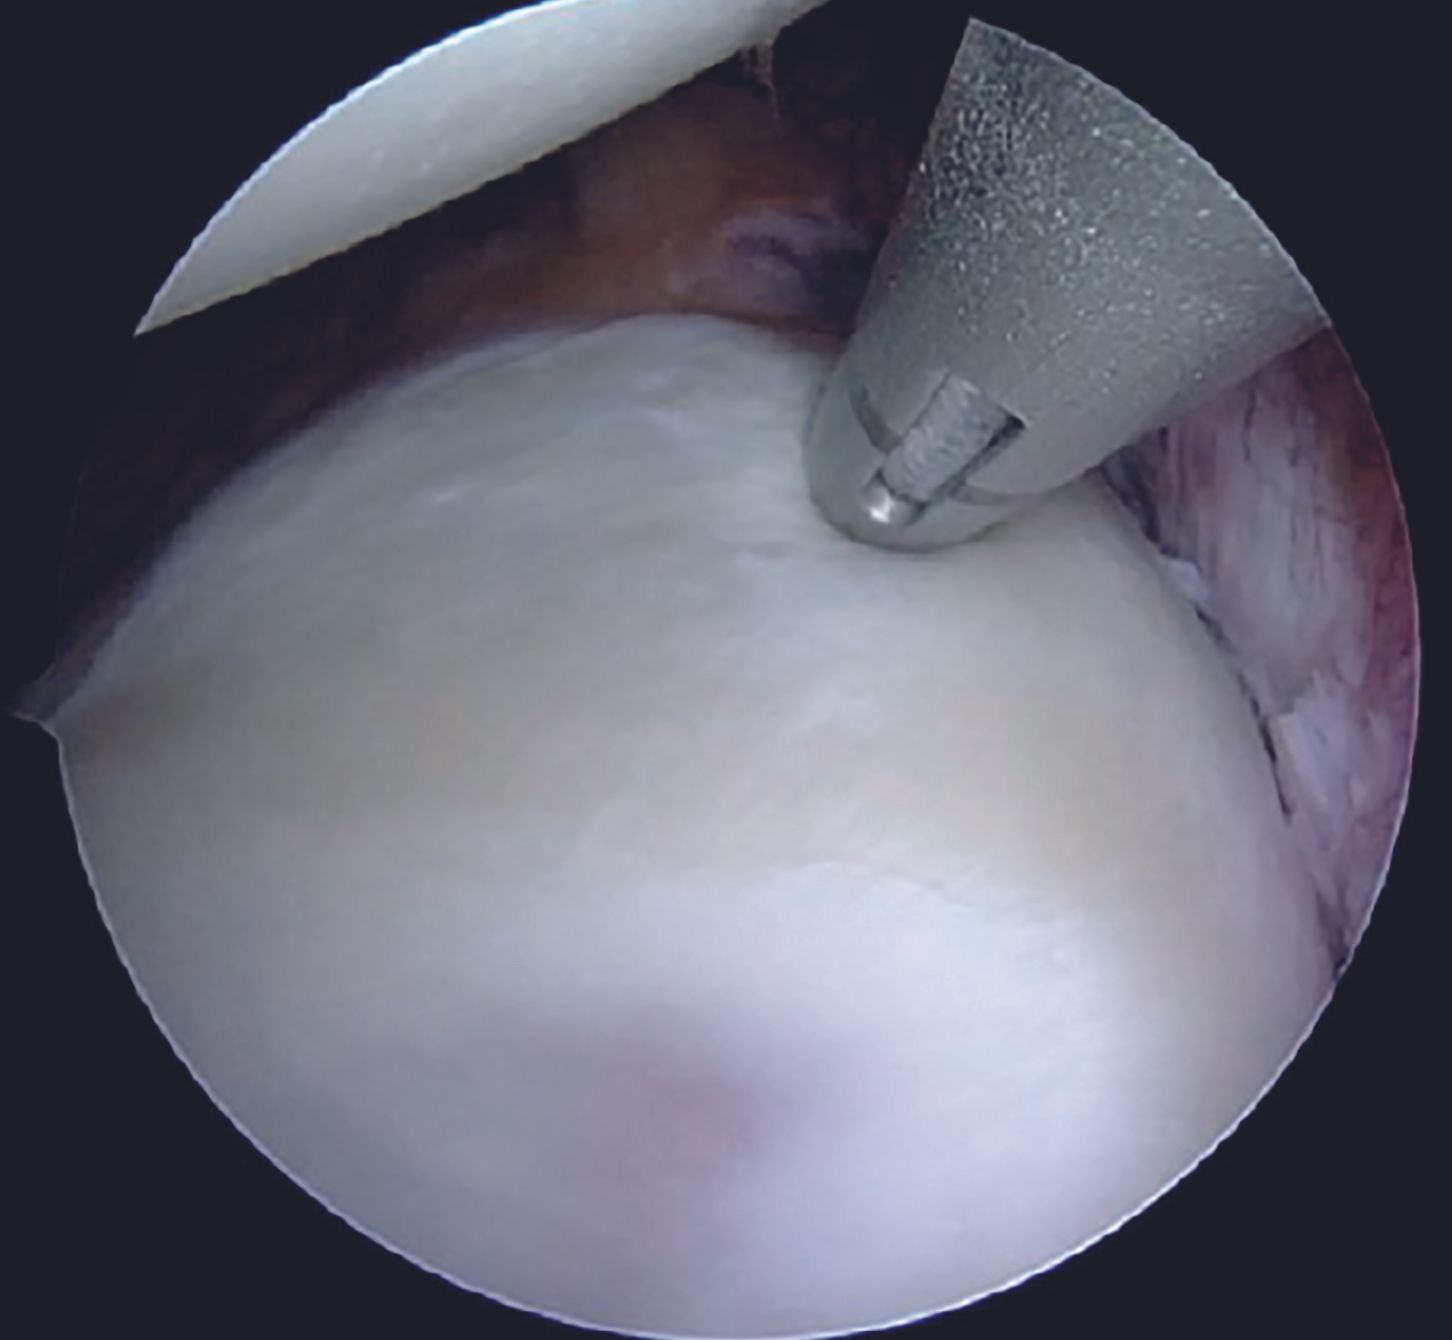

For an isolated Bankart lesion, 3 anchors are usually sufficient. Our preferred choice for the anchor is 1.8mm all-suture anchor as the affected patients are young and thus possess a good quality of the subchondral bone. Advantages of all-suture anchors such as absence of metal implants, no interference with post-operative imaging, easier revision, are well known. Anchor with a tape is preferable to avoid cut-through through the labral tissue. Inferior most anchor is placed first at 5-5.30 O'clock position after drilling a hole using a sleeve through the AI portal (Figure 9). After tapping the anchor in, it is important to pull the tapes so that the anchor bunches up beneath the subchondral bone (Figure 10). Free passage of the tapes is ensured.

Care is taken to keep the knots away from the face of the glenoid by using the shuttled tape as a post and the other one as a throw. Before tying the sliding knot, utmost attention should be paid to provide adequate tension to the labral tissue by pulling the labrum superiorly with a grasper. Tapes are cut with an arthroscopic cutter around 4 to 5mm distal to the knot. One anchor each is placed at 4 and then at 3 O'clock position following a similar steps. After completion of the repair (Figure 15, 16), its integrity and stability is confirmed with a probe. After a thorough wash, closure is done with mattress sutures using 3-0 Ethilon.